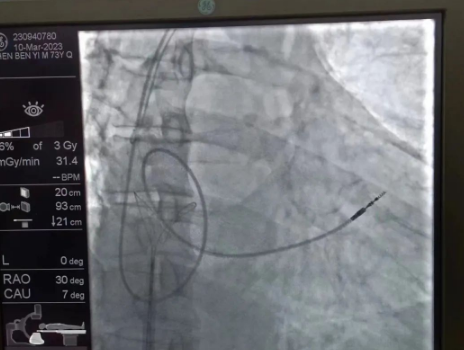

術(shù)中,孫書(shū)紅醫(yī)師首先切開(kāi)起搏器囊袋,游離出起搏器脈沖發(fā)生器,發(fā)現(xiàn)起搏電極完全斷裂,連接于起搏脈沖發(fā)生器,殘端約10cm;考慮患者為起搏依賴患者,需再次植入新的起搏電極導(dǎo)線,穿刺了腋靜脈,放置導(dǎo)絲;同時(shí),李偉杰教授穿刺了左、右股靜脈,于右股靜脈置入了”抓捕器”,左股靜脈備用臨時(shí)起搏通路,以防術(shù)中出現(xiàn)心跳驟停。為了準(zhǔn)確抓捕到心房?jī)?nèi)的在逃起搏電極,李偉杰教授將導(dǎo)管室的X光機(jī)球管調(diào)整成了冠脈模式,這就意味著在抓捕過(guò)程中,醫(yī)生要比平時(shí)的手術(shù)“吃”更多射線……

在透視模式下,抓捕全憑醫(yī)生的經(jīng)驗(yàn)與手感,一次次嘗試,一次次失敗,在場(chǎng)外觀摩手術(shù)的醫(yī)生同樣為李偉杰教授捏了一把汗,“找到了!”電子屏里抓捕器向在逃起搏電極“發(fā)起進(jìn)攻”,一把逮住并順利拔出一根長(zhǎng)達(dá)58cm的起搏電極。